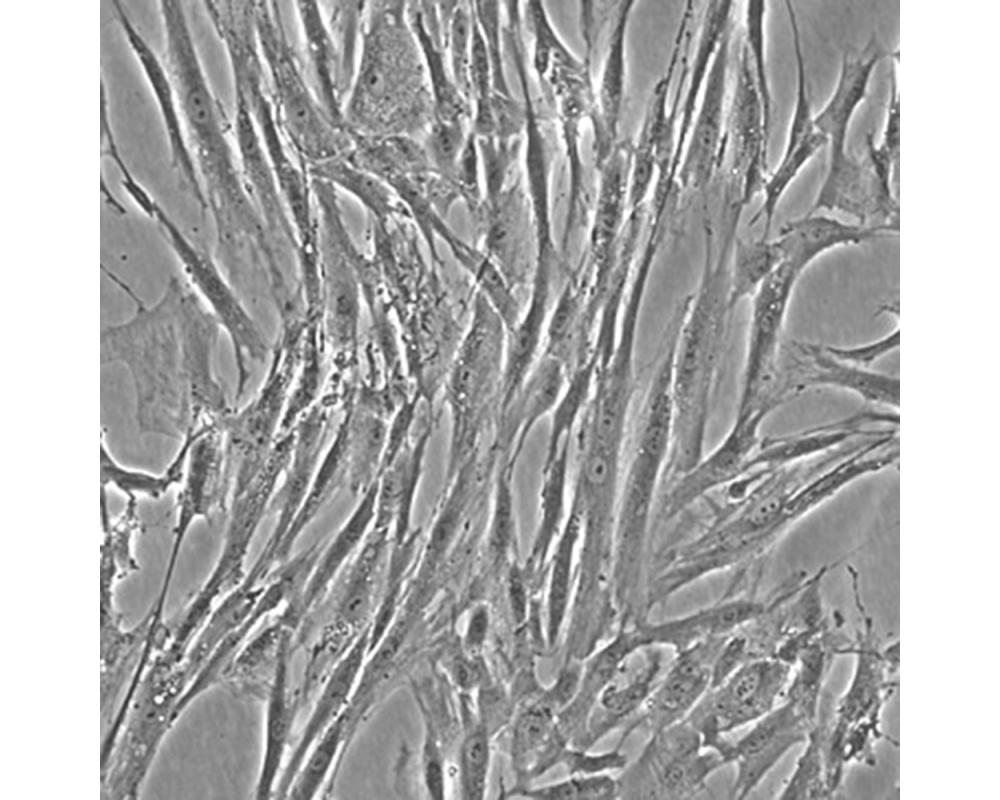

產品名稱 Hs 606.T

中文名稱 人乳腺癌細胞

組織來源 乳腺癌;女性

生長特性 貼壁

培養基 H-DMEM,90%;FBS,10%;雙抗。